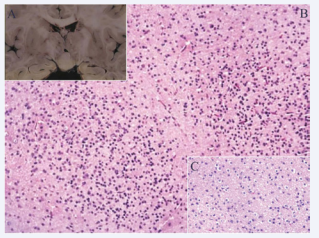

Hamartoma is a term used to describe a disorganized mass of otherwise normal cellular elements that rarely invades surrounding structures, in this case, the hypothalamus. Macroscopically the HH are solitary lesions, well-defined round or ovoid soft tissue masses that seems normal brain tissue, that vary in size in diameter, from some millimeters to widespread mixed solidcystic lesions measuring several centimeters (Figure 2A).

Courtesy of Dr. Ignacio A. Felix. (A) - Coronal section of the brain  through the plane of the mammillary bodies reveals a right-side type III HH  (B) - Hematoxylin and eosin section through the HH showing cluster of small  neurons amongst a background of neuropil-like stroma with individual neurons  and diffusely astrocytes between the nodules. Original magnification: 100x. (C)  - Higher magnification 400x.

Figure 2: Courtesy of Dr. Ignacio A. Felix. (A) - Coronal section of the brain through the plane of the mammillary bodies reveals a right-side type III HH (B) - Hematoxylin and eosin section through the HH showing cluster of small neurons amongst a background of neuropil-like stroma with individual neurons and diffusely astrocytes between the nodules. Original magnification: 100x. (C) - Higher magnification 400x.

Calcification, hemorrhage, and necrosis are not common whilst huge lesions often contain well-delineated cysts. Unde the microscope display a HH consist of disorganized networks of well-differentiated small and large neurons interspersed with variable amounts of astrocytes, not very different from respects to other structural lesions associated with other epileptic syndromes. Characteristically presents nodules or neuronal groups [52]. These nodules may vary in size and are composed predominantly of small neurons. A neuropile rich in glia surrounded these nodules with a few interspersed large ganglion cells [19] (Figure 2B and C).